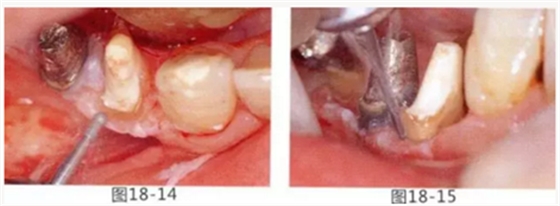

圖18-14 使用圓頭金剛車針進(jìn)行骨外科處理。

圖18-15 使用鎢鋼車針去除殘留在牙根面的纖維。